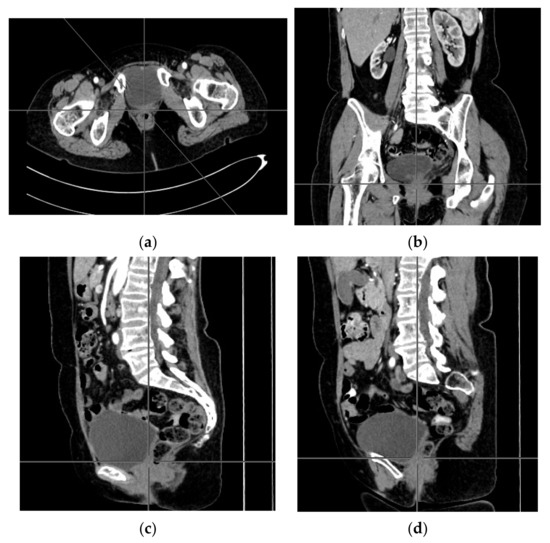

A computer tomography of the abdomen and pelvis was also performed every 3 months for the possible detection of ovarian cancer recurrence. No CT changes suggestive of recurrence were observed in the patient during the treatment. There are illustrates scans on the same section from CT performed at the beginning of PARP inhibitor treatment (Figure 2) and before 48 cycle of olaparib chemotherapy (Figure 3).

Figure 2.

(a–d) CT scans performed at the beginning of olaparib treatment.

Figure 3.

(a–d) CT scans performed before 48 cycle of olaparib treatment.